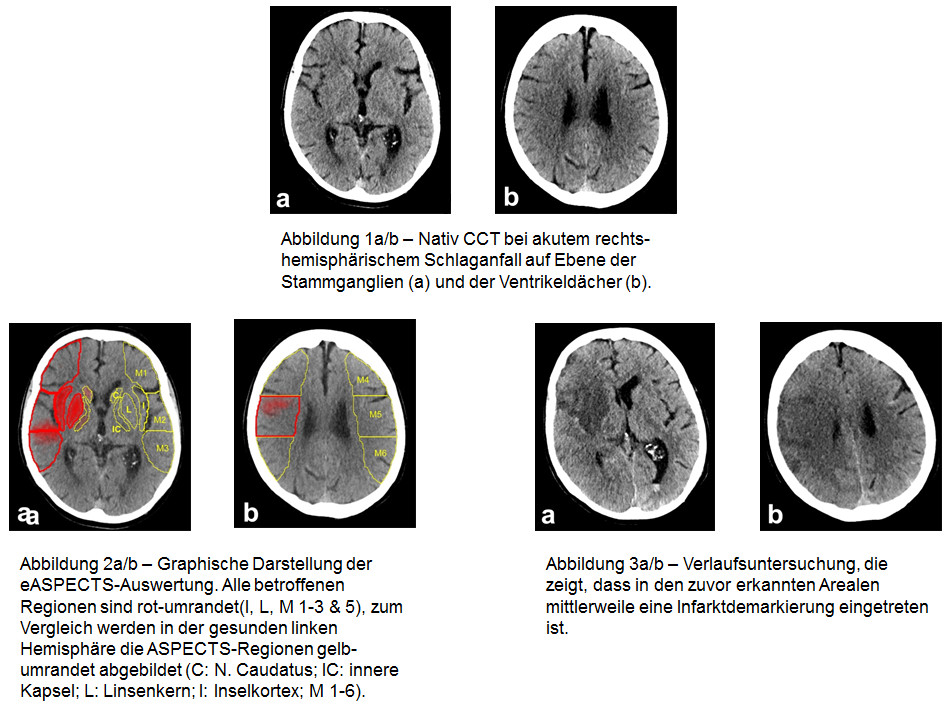

In den großen klinischen Studien erhielten vor allem solche Patienten eine Thrombektomie, deren Schlaganfall in der CT-Untersuchung einen gewissen Schweregrad nicht überschritten hatte. Dieser Schweregrad wird üblicherweise anhand eines Scores ermittelt, der „Alberta Stroke Programme Early CT Score“, kurz ASPECTS. So durfte der ASPECTS in den meisten erfolgreichen Studien (etwa ESCAPE und SWIFT-PRIME, REVASCAT) nicht schlechter als sechs oder sieben Punkte sein. Der Maximalwert beträgt zehn Punkte.

Die Bestimmung des ASPECTS ist Standard bei Patienten, die wegen eines frischen Schlaganfalls eine CT-Untersuchung erhalten. „Die manuelle Ermittlung dieses Scores erfordert aber ein hohes Maß an Erfahrung und ist anfällig für Fehleinschätzungen“, betont Herweh. Abhilfe schaffen könnte eine softwarebasierte Ermittlung des ASPECTS. „Sie ist objektiver und kann die Prognose der Patienten möglicherweise besser abschätzen als Radiologen dies können.“

Mit eASPECTS von Brainomix existiert seit einiger Zeit eine solche Software, die zunehmend ihren Wert in klinischen Studien unter Beweis stellt. Dr. Herweh berichtet über die aktuellsten Daten beim 98. Deutschen Röntgenkongress / 8. Gemeinsamen Kongress der DRG und ÖRG (24.-27. Mai 2017, Leipzig). In einer ersten Validierungsstudie mit 34 Patienten konnte gezeigt werden, dass die softwarebasierte Auswertung der CT-Bilder der Auswertung durch Radiologen mit wenig Training überlegen und der durch Experten gleichwertig ist. Eine weitere, britische Studie hat bei 132 Patienten bestätigt, dass die Software im Vergleich zu Neuroradiologen nicht unterlegen ist.

Die Software funktioniert also technisch gesehen. Aus klinischer Sicht ist die eigentlich interessante Frage aber, ob sie geeignet ist, besser als oder zumindest genauso gut wie Experten vorherzusagen, welche Patienten einen schlechten klinischen Verlauf haben. Dazu haben Herweh und Kollegen jetzt eine dritte Studie durchgeführt. Bei 212 Patienten mit frischem Schlaganfall wurde rückblickend der ASPECTS durch drei Experten und durch die Software ermittelt. Das Ergebnis wurde dann mit dem tatsächlichen klinischen Verlauf der Patienten korreliert.